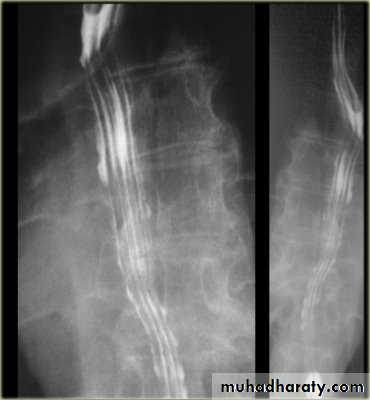

Achalasia continue

5. DILATATION (Sac like in proximal part )6-Undulating or spiky out line due to sluggish peristalsis.

7 Non- homogeneity of Barium due to food particles.

8-Air Barium level.

9- CXR shows widening of mediastinum.

10-Absence of fundal gas shadow.

7-Basal fibrosis in lungs due to repeated aspiration pneumonia .

LEFT: Dilated esophagus (arrows) appears as long, well-defined structure paralleling heart RIGHT: Dilated esophagus usually deviates to right. Narrowing (arrow) at hiatus.